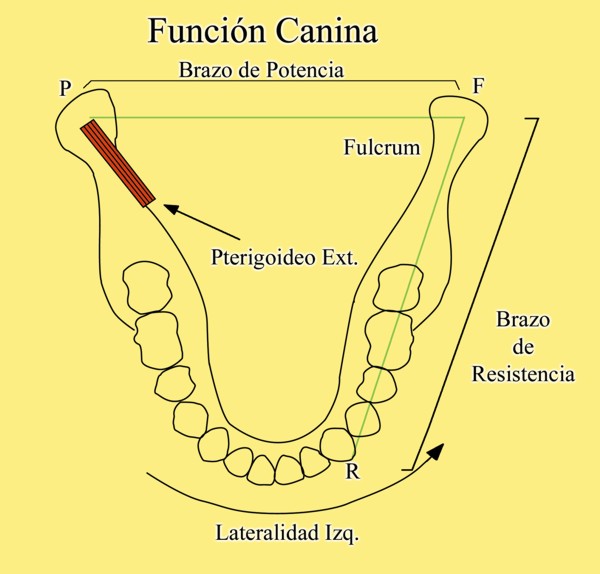

RESUMEN Más allá en el tiempo, respecto de las razones más frecuentes de fracasos como temperatura de fresado, infecciones, falta de fijación inicial, falta de higiene, etc., la OCLUSIÓN recibe sobre sí, la responsabilidad de la permanencia de la osteointegración, como así de la ortofunción del sistema todo. Sometimes ago,conserning the most frecuent reason of failures such as the strawberry action temperature, infections and lack of hygiene…etc.,the OCLUSION has itself the responsability af having the osteointegration well as the allsistem ortofunction . DESARROLLO La valoración de los fracasos en IMPLANTOLOGÍA es difícil de contabilizar sobre todo después del año, ya que el confort logrado por lo general, hace que el paciente realice correctamente sus primeros controles, y después; apoyado en su bienestar; intente subconscientemente olvidar ese período de su vida, que si bien le devolvió su capacidad masticatoria, fonética, social, etc., le ocasionara gastos, molestias, sufrimientos. … la APLICACIÓN de dichas fuerzas, requiere de una exactitud mucho mayor. Los esquemas propuestos a través de los años, no son muchos ni muy variados… I-Evitar las fuerzas tangenciales. II-Repartir las fuerzas lo máximo posible. Sin embargo, muchas veces se confunden los conceptos anteriores con criterios inexactos. Por ej: a-Reducción de las caras vestibulares y palatinas, aceptando que la menor superficie de intercontactos reduce la carga. b-Utilización de la Función de Grupo Posterior, en la creencia de que repartiendo el esfuerzo en las piezas posteriores, ganamos resistencia; a la potencia ejercida por los músculos. c-No permitiendo el contacto excéntrico de un canino implantado, para aliviarlo de las cargas laterales, sobre cargando de esta manera la tabla premolar-molar en el Lado de Trabajo. Algunos conceptos aislados, que forman parte de toda una filosofía de la Oclusión (OCLUSIÓN ORGÁNICA), sean tal vez de ayuda para echar luz sobre los preceptos anteriores. 1º-PROPORCIONES FUNCIONALES DE UN PAR OCLUSAL En la figura siguiente, observamos la relación final masticatoria de un PAR OCLUSAL: En el se ven los contactos puntiformes, producto del choque de superficies redondeadas contra superficies redondeadas («Solo pueden encontrarse en un punto» Ref: Principios Mecánicos Esferoidales.W.Mc.Horris.) Si Miramos con atención este tipo de contactos interoclusales, veremos que la superficie actuante es mucho menor que la superficie total de la cara oclusal: 45% (Fig.1) Por lo tanto, si no es por razones del Pilar de Emergencia para no crear un espacio biológico inadecuado… ¿POR QUÉ REDUCIR LA CARA OCLUSAL VESTÍBULO LINGUALMENTE? (Figs. 2-3-4-5) Si observamos con atención las figuras 2-3-4-5, veremos desde todos los planos , que el área contactante es muy reducida respecto del ancho oclusal total, siendo las fuerzas resultantes , AXIALES al eje implantario. 2º-FUNCIÓN DE GRUPO POSTERIOR. FUNCIÓN CANINA. Tres son las razones por las cuales nos inclinamos a la utilización de la Función Canina. En cambio, en el esquema de FUNCIÓN CANINA, podemos observar que el BRAZO DE POTENCIA, es prácticamente igual al de RESISTENCIA, equilibrando de esta manera la palanca y destruyendo mucho menos las estructuras de soporte(Interface I-H) (Fig. 7) Otra de las razones de peso en este tema es la DIFERENCIA DE ANGULACIÓN que existe entre la cara palatina del canino y las vertientes contactantes del sector premolar-molar. A MAYOR ANGULACIÓN, MENORES FUERZAS LATERALES(Perpendiculares al Plano), y por lo tanto , menor destrucción de la interface Hueso-Implante(Figs. 9-11). DIFERENCIAS EXCITATORIAS DE LOS GRUPOS MUSCULARES. Por último debemos considerar que el intercontacto dentario del sector anterior, estimula excitatoriamente a las fibras anteriores y verticales del temporal (Figs.12-13-14-15), mientras que los contactos posteriores lo hacen con la cincha pterigo-maseterina(Fig. 16-17-18-19) Por lo tanto ,si se comprende el fisiologismo de estos conceptos, es sencillo entender que la sobrecarga de los sectores posteriores es nocivo generando fuerzas tangenciales de Alto Potencial Patológico. 3º-FUNCIÓN DE GRUPO ANTERIOR Las ventajas de un Brazo de Resistencia mayor se acentúan cuando tenemos el esquema de FUNCIÓN DE GRUPO ANTERIOR. Además, debemos tener en cuenta que, durante la función de un Ciclo Masticatorio, es más importante la Desoclusión Final que la Desoclusión Inicial, ya que al ser más larga esta última, es durante el transcurso de su deslizamiento cuando se ejercen fuerzas laterales mayores(Fig. 21) A medida que la punta del canino inferior se acerca a la O.R.C., o sea al Punto de Contacto Intercanino, las fuerzas laterales disminuyen en virtud del acortamiento del brazo de potencia de la palanca, hasta que, al terminar su recorrido, la fuerza es proyectada axialmente sobre el eje del canino superior, debido a que, al margen de la intensidad que la fuerza trae durante el cierre, la dirección de la misma «apunta» en esa dirección. Por eso decimos que los caninos Axializan el Ciclo Masticatorio. Si estamos imitando en lo posible a la naturaleza, no olvidemos este detalle que los dientes naturales provéen, para evitar las fuerzas laterales del canino a la hora de realizar la supraestructura coronaria del mismo. Es ahora menester acentuar que la problemática concreta se manifiesta, no durante la función, sino durante la PARAFUNCIÓN… Cuando estudiamos recorridos de la Dinámica Mandibular, desde el conocido Bicuspoide de Posselt hasta cualquiera de los registros pantográficos, estamos invirtiendo la dirección del movimiento… A.- El primer premolar es el más anterior de la tabla oclusal posterior. Por lo tanto el brazo de resistencia es el mayor de dicha tabla. B.- El lateral, como parte del grupo anterior, cuenta con un empotramiento tipo «clavo largo», y el interseptum lateral -canino, que se opone a la fuerza, es mucho más grueso que la tabla vestibular del primer premolar(Fig.23) C.- Condiciones, las dos anteriores que se favorecen considerablemente, si al enfundar el lateral se logra junto al central una Función de Grupo Anterior. D.- De manera más artificiosa, la instalación de una placa de relajación, soluciona durante la noche lo nocivo de las fuerzas laterales. Veamos un par de casos, como ejemplo de lo dicho: Paciente de 54 años que se presenta a la consulta portando prótesis completa superior y antagonista natural que soporta fundas de porcelana. Obsérvese la función de grupo posterior ejercida, y las consecuencias de la misma: Otro paciente que presenta fractura de la cúspide fundamental de un onlay de porcelana antagonista de cinco piezas implantadas (Fig.27). Radiográficamente se observa la desinserción de uno de sus abuttments cementados (Fig.28). En el Lado de Trabajo (LT), no existe el canino encargado de desocluir la zona afectada (Figs.29-30) Como corolario, cabe entonces una pregunta: ¿Es el Implante en el canino quien debe preservar de patología oclusal al resto del sistema…. ¿Es el Implante…un medio…o un fín? BIBLIOGRAFÍA 1- Dibujos tomados del libro del mismo autor: «OCLUSIÓN ORGÁNICA… UN CAMINO HACIA LA REHABILITACIÓN ORAL»(en preparación) 2- «NEUROFISIOLOGÍA DE LA OCLUSIÓN» 3- «OCLUSIÓN Y FUNCIÓN» 4- «FUNDAMENTOS, TÉCNICAS Y CLÍNICA EN REHABILITACIÓN BUCAL» 5- «OCLUSIÓN Y REHABILITACIÓN» 6- «DISFUNCIÓN TEMPOROMANDIBULAR» 7- «PROCEDIMIENTOS CLÍNICOS Y DE LABORATORIO DE OCLUSIÓN ORGÁNICA» 8- «ESTUDIO ELECTRÓNICO DEL MOVIMIENTO MANDIBULAR» 9- «OCLUSIÓN: CONCEPTO PARA EL CLÍNICO» 10- «IMPLANTOLOGÍA CONTEMPORÁNEA» 11- «OCLUSIÓN Y DIAGNÓSTICO EN REHABILITACIÓN ORAL» 12- «PRINCIPIOS DE OCLUSIÓN»

En un esquema de lateralidades a la izquierda, observamos que el Fulcrum de la misma lo encontramos en el cóndilo izquierdo, Cóndilo de Trabajo, la Potencia se encuentra en la fuerza generada por el Pterigoidéo Ext. del lado derecho, Cóndilo de No Trabajo, y la resistencia se dispone, en el caso de una FUNCIÓN DE GRUPO, en las Crestas Triangulares Internas de la tabla premolar-molar superior, que rozan contra las Crestas Centrales antagonistas ,correspondientes al inferior.

Por lo tanto, el Brazo de Potencia se establece entre el CnT(POTENCIA),y el CT(Fulcrum), mientras que los Brazos de Resistencia de las distintas piezas que intervienen en la Función de Grupo, se encuentran entre estas piezas y el CT(Fulcrum).

Como podemos ver en el esquema, estos son menores que el Brazo de Potencia y por lo tanto la fuerza generada por el mismo, producirá mayor deterioro , pues la palanca no está equilibrada:

EL BRAZO DE POTENCIA ES MAYOR QUE EL DE RESISTENCIA (Fig.6)